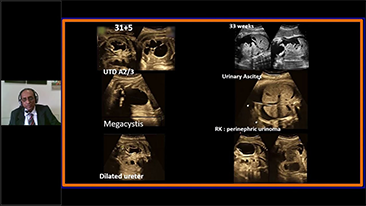

Com a plataforma ZST+ avan?ada, as solu??es inteligentes full-stack do Nuewa s?o projetadas especialmente para melhorar a saû¤de da mulher durante toda a gesta??o, desde o perûÙodo que antecede ao que procede û gravidez e û recupera??o pû°s-parto, a fim de oferecer diagnû°sticos abrangentes e eficientes para atender aos desafios clûÙnicos cada vez mais exigentes.